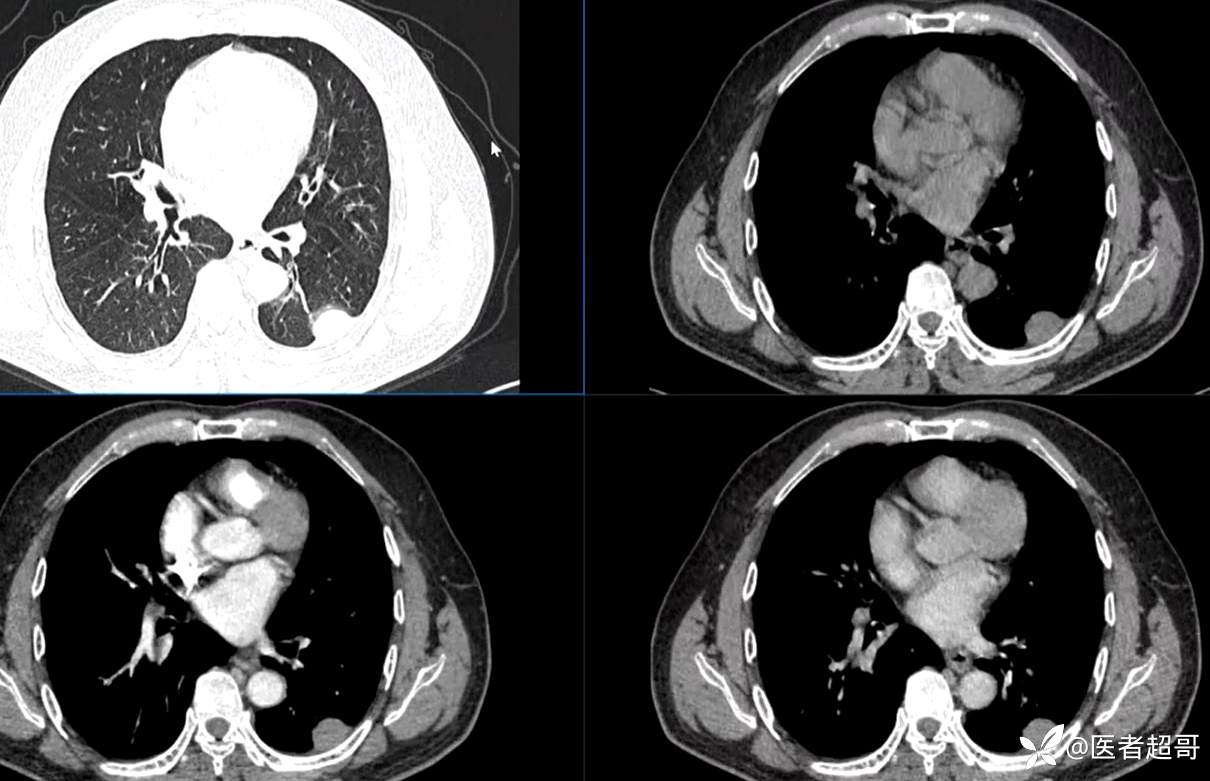

现病史:患者5月前因咳嗽、咳痰于当地医院就诊,完善胸部CT提示:胸膜多发占位,期间患者无胸闷、气紧、咳嗽、咳痰、心慌等不适,患者于我院门诊行胸部CT提示:左下胸膜增厚并见多个软组织密度结节影局限性凸起,较大者大小约3.5x2.2cm,增强扫描呈持续性轻度强化,考虑肿瘤性病变可能性大;门诊遂以:胸膜肿瘤收入我科。